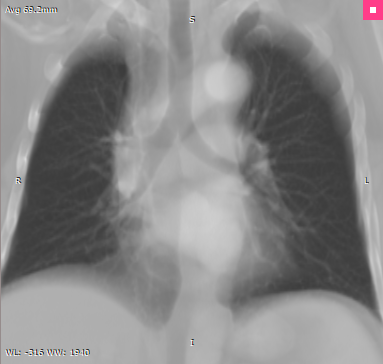

Avg |

•Avg (Average)